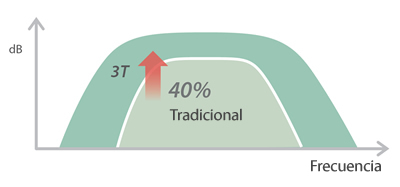

X-Insight es la soluci├│n intuitiva para una mejor visualizaci├│n.

Bas├Īndose en una profunda comprensi├│n de las necesidades del usuario, el sistema de ultrasonidos DC-60 Exp con X-Insight est├Ī dise?ado para ofrecer una alta eficiencia con im├Īgenes de precisi├│n, la cual se ve potenciada por una claridad inmediata, una inteligencia excepcional y benefici├Īndose de una c├│moda experiencia.